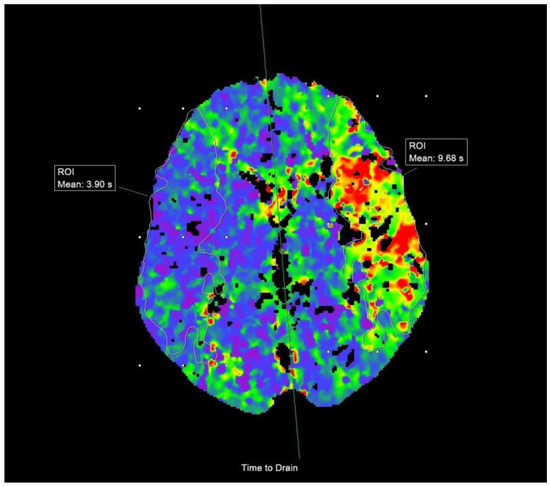

2.3. Imaging Data and Analysis